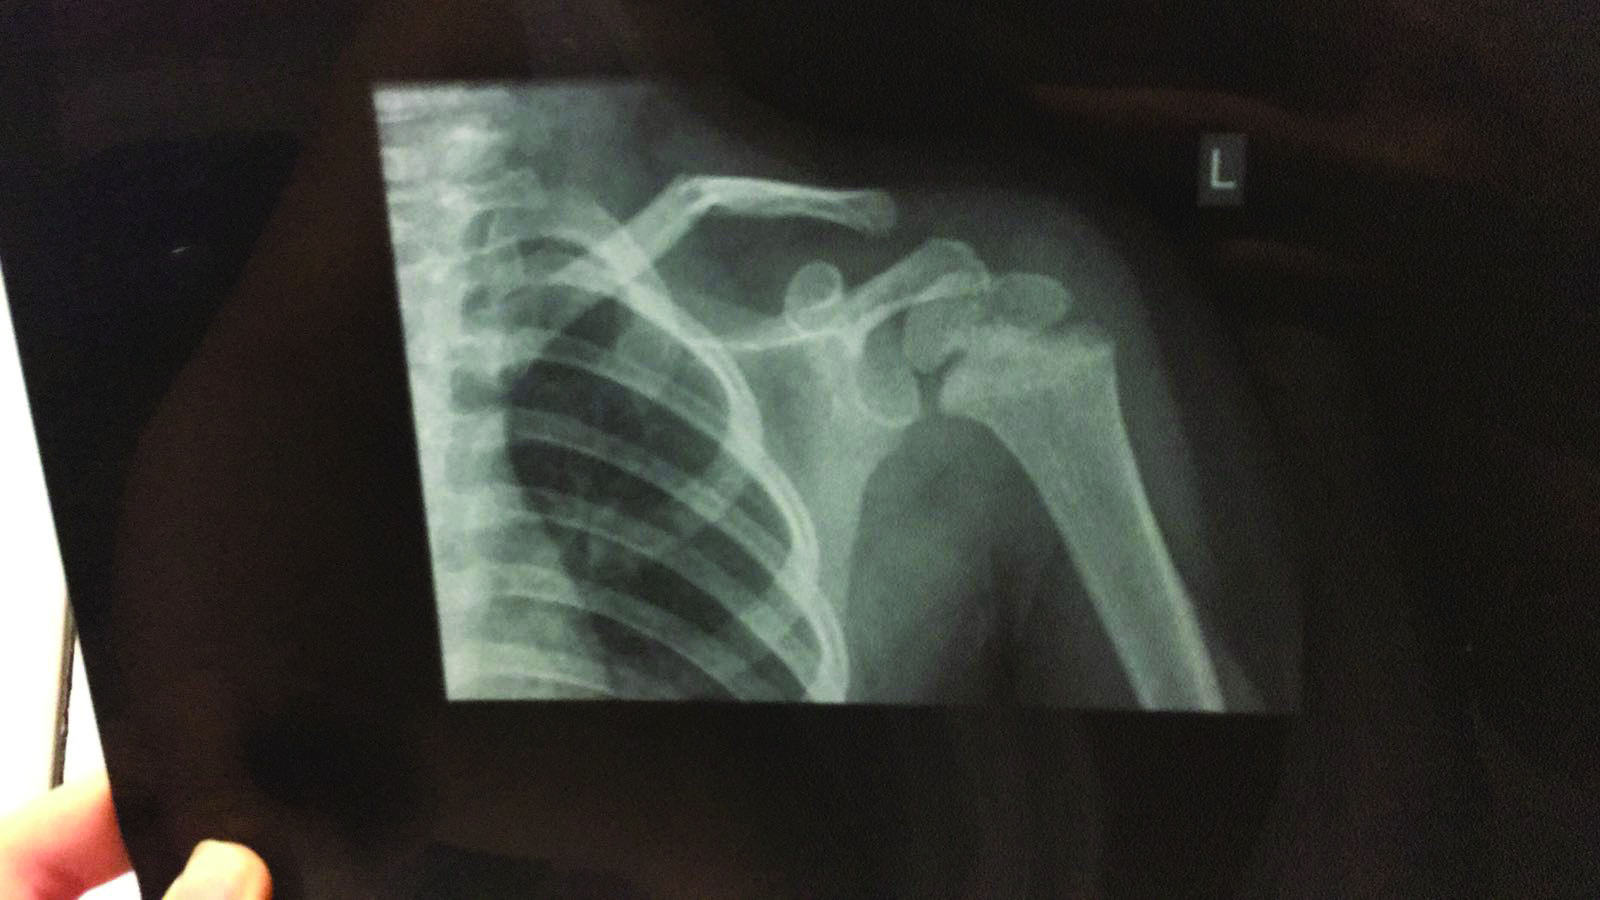

“I knew something isn’t right as my daughter was in wrenching pain. I contacted the school to clarify what has happened to my daughter but reached a dead-end, as I was told by the educator responsible for my daughter’s class that she was not allowed to speak to parents. They weren’t cooperative at all, and when I threatened that I will take the matter to the police if they continue to deny informing me about what happened to my daughter, another teacher told me that she took a tumble from the slide,” she explained. The worried mother immediately took her daughter to the hospital after suspecting the behaviour of the teachers. At the hospital, X-ray examinations showed that Fatima suffered from a fractured shoulder. Um Fatima told that the school continued to deny their responsibility of her daughter’s injury.